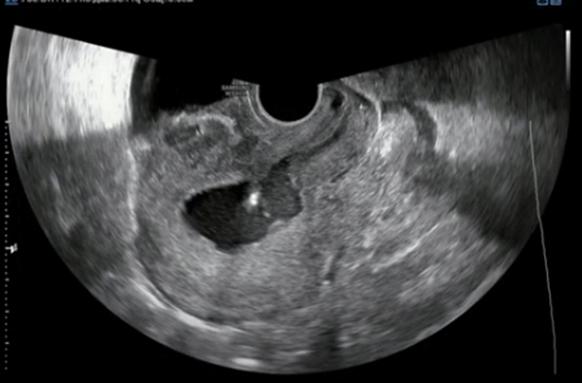

Эндометрий после кесарева